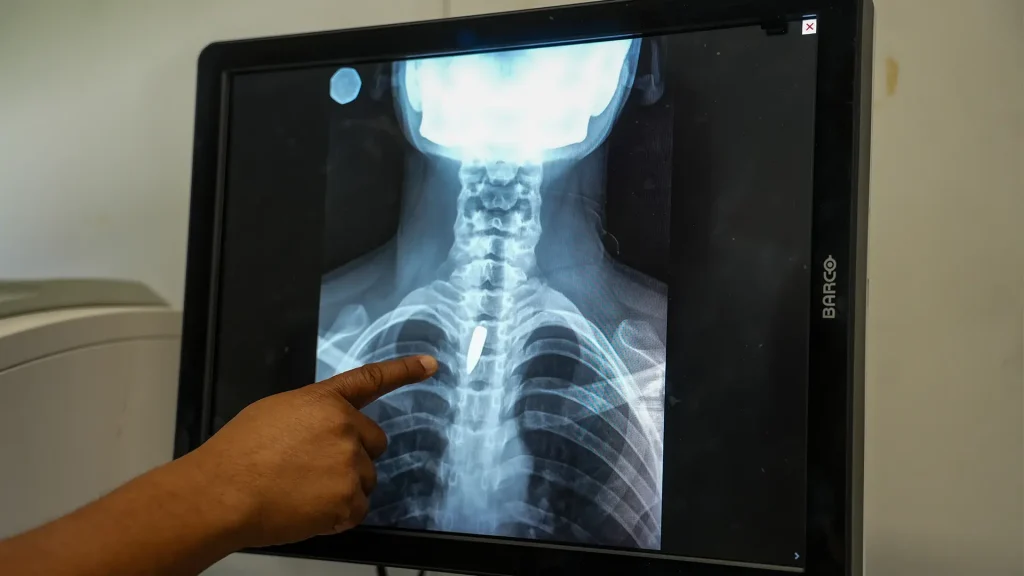

Una radiografía muestra una bala alojada en el pecho de Linda. Los cirujanos determinaron que era demasiado arriesgado extraerla, por lo que tendrá que seguir viviendo con ella. Linda fue alcanzada mientras estaba en la iglesia, cuando un grupo armado abrió fuego contra un helicóptero que se cree está vinculado a la policía. Puerto Príncipe, Haití, enero de 2026.

Una radiografía muestra una bala alojada en el pecho de Linda. Los cirujanos determinaron que era demasiado arriesgado extraerla, por lo que tendrá que seguir viviendo con ella. Linda fue alcanzada mientras estaba en la iglesia, cuando un grupo armado abrió fuego contra un helicóptero que se cree está vinculado a la policía. Puerto Príncipe, Haití, enero de 2026. © Marx Stanley Léveillé/MSF